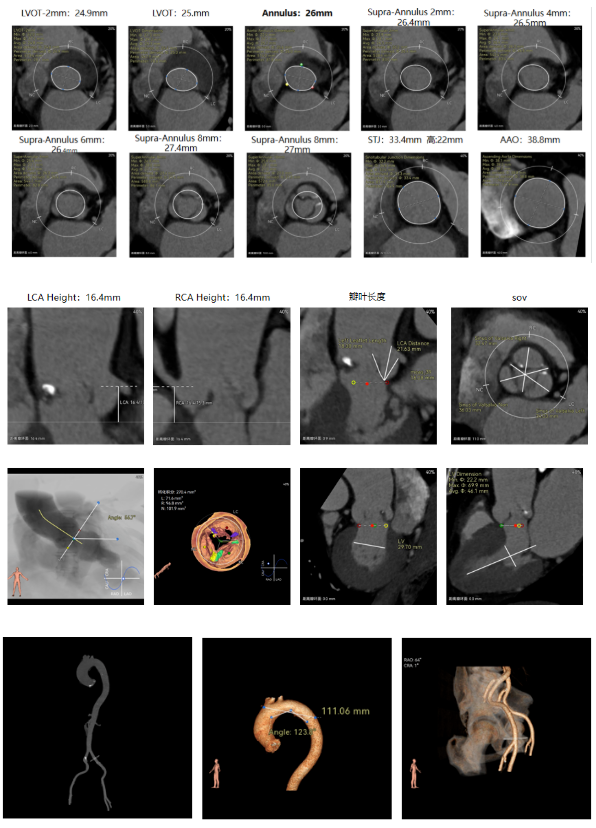

术前CT

反流为主,三叶瓣右无部分融合,轻度钙化存在融合脊,主动脉瓣环径26mm,LVOT直径25mm,瓣上限制轻。双侧冠脉开口高度可,瓣叶长度小于冠脉开口上缘到主动脉根部的距离,窦部空间较大。左室内径正常,主动脉瓣环水平夹角56.7°;外周双侧入路内径可,髂外动脉存在散在钙化,右股低分叉,主动脉弓距弓角可。